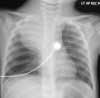

DISCUSSION: In addition to the lateral neck mass, physicians in the emergency department noted dilated superficial vessels on the right anterior chest wall (Figure 1). A chest radiograph demonstrated a large density in the right upper lobe with a mediastinal shift to the left side (Figure 2).